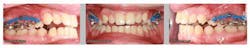

Case report

A healthy 15-year-old male presents to the clinic with an anterior open bite. His case is outlined in the figures below.

The patient in the above case report is still in active treatment. Now that successful maxillary posterior intrusion has been accomplished, the remaining full, fixed orthodontic appliances can be placed. The TPA can be removed and the molar intrusion will be held for the remainder of treatment with a ligature tie placed from the first molar to the TADs. The TADs will be kept in place for the remainder of treatment to maintain the stability of the intrusion as bone remodeling occurs.